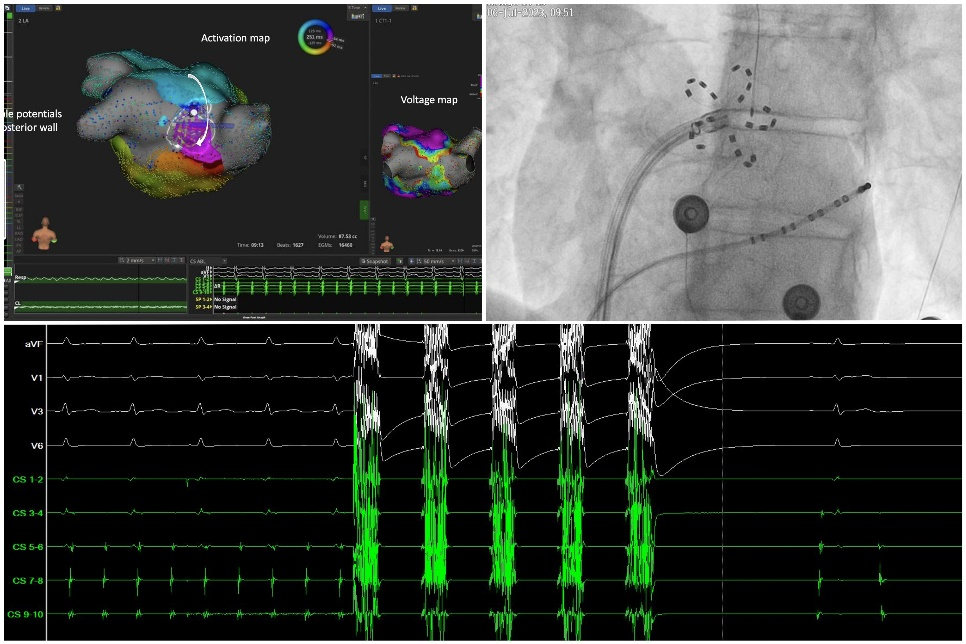

“一次放电,电位就消失了!”

是FARAPULSE手术开展时,临床医生最多的感叹。100%的手术中肺静脉实现即刻隔离。

FARAPUSLE充分的临床研究证明,即刻隔离率100%3,3个月肺静脉复标测96%隔离率2,一年阵发房颤手术成功率90%4。

FARAPULSE是专为房颤脉冲消融设计的网篮+花瓣状导管,全电场覆盖口部及前庭,提升消融效果

FARAPULSE的标准32次放电手术流程,操作简单,手术时间可控